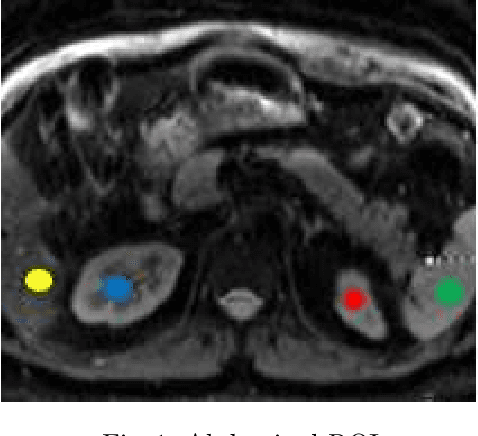

Abstract:Kidney DCE-MRI aims at both qualitative assessment of kidney anatomy and quantitative assessment of kidney function by estimating the tracer kinetic (TK) model parameters. Accurate estimation of TK model parameters requires an accurate measurement of the arterial input function (AIF) with high temporal resolution. Accelerated imaging is used to achieve high temporal resolution, which yields under-sampling artifacts in the reconstructed images. Compressed sensing (CS) methods offer a variety of reconstruction options. Most commonly, sparsity of temporal differences is encouraged for regularization to reduce artifacts. Increasing regularization in CS methods removes the ambient artifacts but also over-smooths the signal temporally which reduces the parameter estimation accuracy. In this work, we propose a single image trained deep neural network to reduce MRI under-sampling artifacts without reducing the accuracy of functional imaging markers. Instead of regularizing with a penalty term in optimization, we promote regularization by generating images from a lower dimensional representation. In this manuscript we motivate and explain the lower dimensional input design. We compare our approach to CS reconstructions with multiple regularization weights. Proposed approach results in kidney biomarkers that are highly correlated with the ground truth markers estimated using the CS reconstruction which was optimized for functional analysis. At the same time, the proposed approach reduces the artifacts in the reconstructed images.